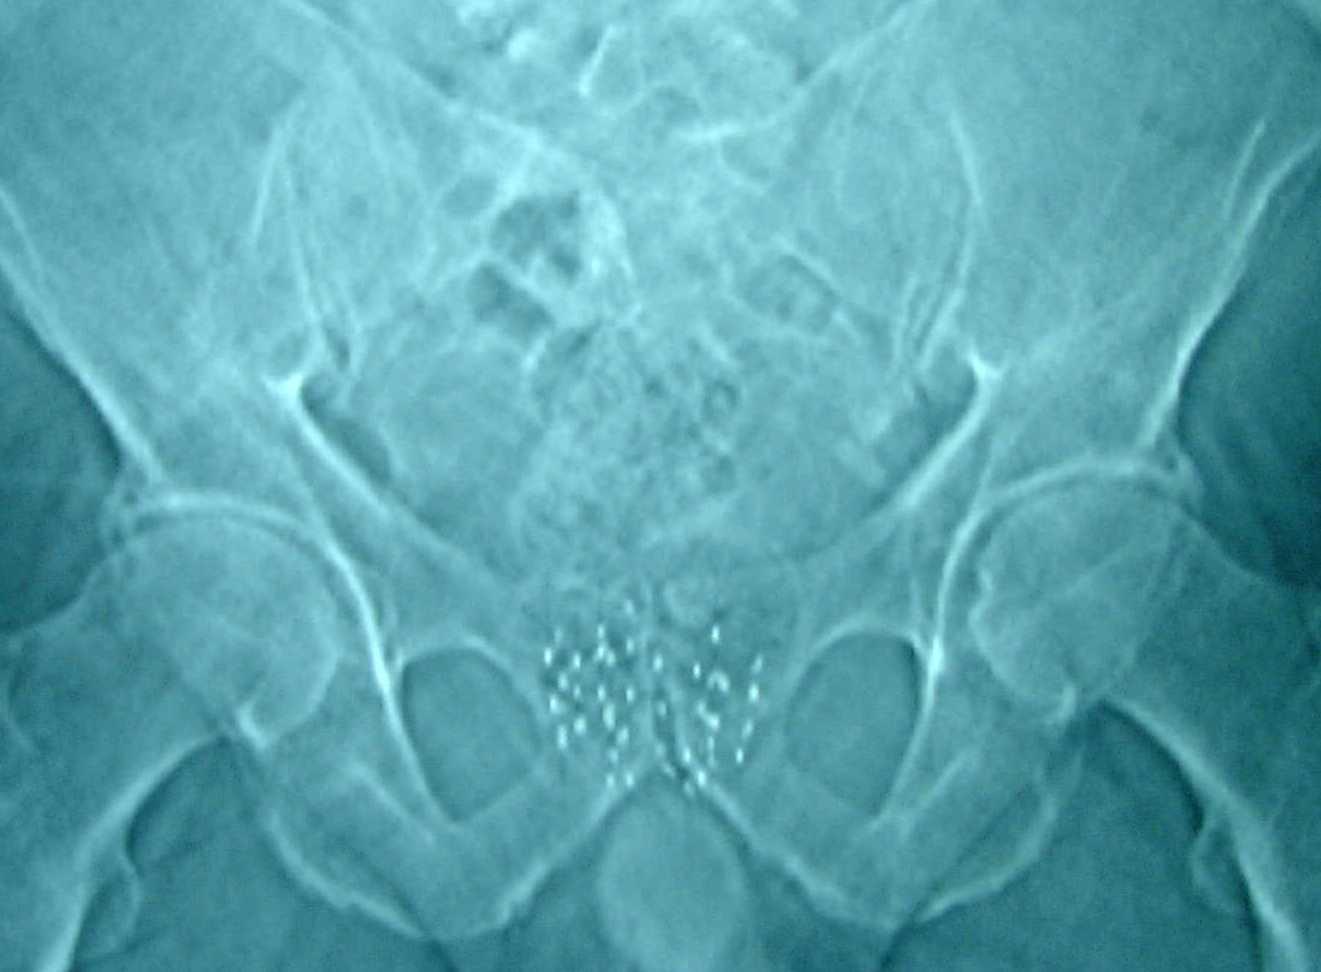

Röntgenfoto van het bekken met Jodium 125 zaadjes